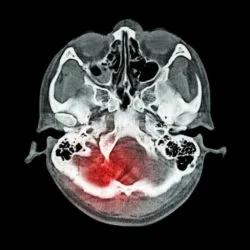

Eliquis Brain BleedA California man claims adverse side effects of Eliquis can cause patients to experience life-threatening internal bleeding events, cerebral hemorrhage, stroke, blood clots and other serious complications.

Shortly after taking the drug under the direction of his physician, Gabriel suffered from adverse side effects of Eliquis that included an intracerebral hemorrhage, and severe pain and suffering.

Eliquis lawsuits, such as Gabriel’s, claim the blood thinner causes side effects such as a brain hemorrhage and other serious internal bleeding side effects.  These serious adverse side effects of Eliquis can be extremely difficult to treat. Warning signs and symptoms of internal bleeding may include:

• Hemorrhagic stroke (brain bleed)

• Intracranial hemorrhage (bleeding in the skull)